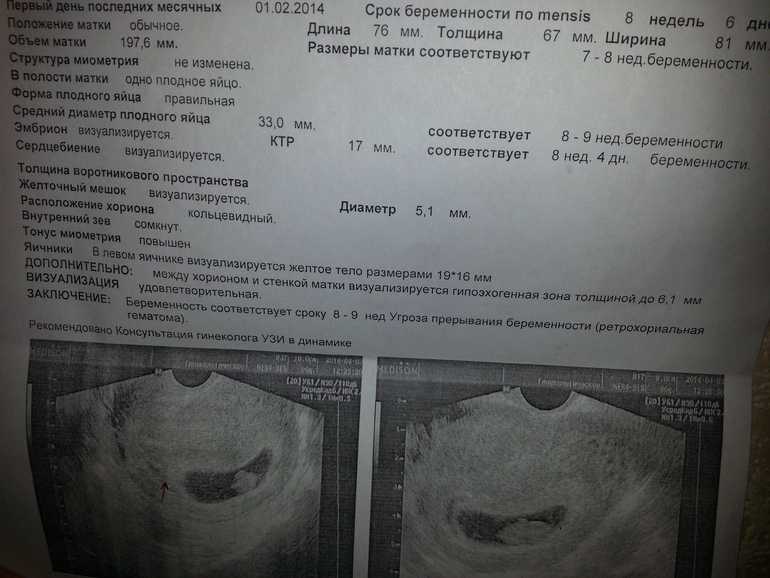

Узи при беременности на раннем сроке.

Информативность узи на ранних сроках беременности

Следите за регулярностью УЗИ, так как мониторинг состояния матки в динамике позволяет выявить возможные отклонения на ранних сроках.